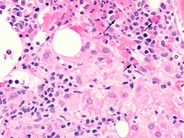

Bone marrow granuloma - 2.

Category: Reactive Marrow

The granulomatous lesion is shown at higher magnification to illustrate the cellular composition of macrophages with eosinophilic cytoplasm and scattered lymphocytes and plasma cells.